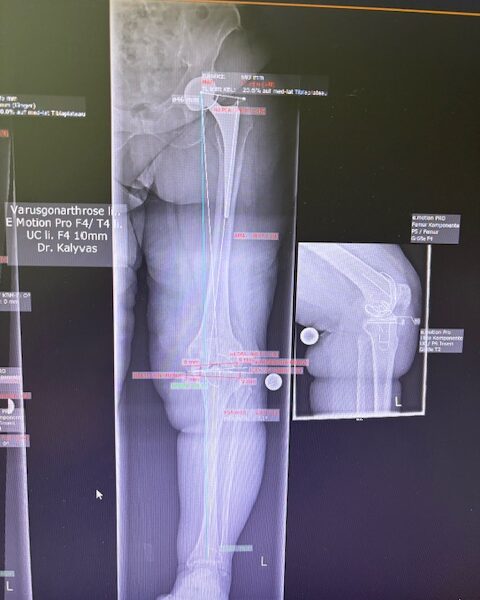

Ο προεγχειρητικός ψηφιακός σχεδιασμός

Πραγματοποιήθηκε σε ειδική ακτινογραφία ολόκληρων των δύο κάτω άκρων. Σε αυτό το ψηφιακό μοντέλο σχεδιάστηκε με ακρίβεια το είδος, το μέγεθος και η ακριβής θέση των προθέσεων, με βάση τα ανατομικά χαρακτηριστικά της ασθενούς.

Ο ψηφιακός σχεδιασμός επιτρέπει απόλυτη εφαρμογή των μοσχευμάτων, ελαχιστοποιώντας τα περιθώρια απόκλισης και εξασφαλίζοντας άριστη ευθυγράμμιση και κινηματική ισορροπία του γόνατος.

Τα εμφυτεύματα που χρησιμοποιήθηκαν στο γόνατο της ασθενούς είναι της Aesculap: E-Motion Pro, μηριαίο μέγεθος 4, κνημιαίο μέγεθος 4, με ενθέμα (inlay) 10mm.